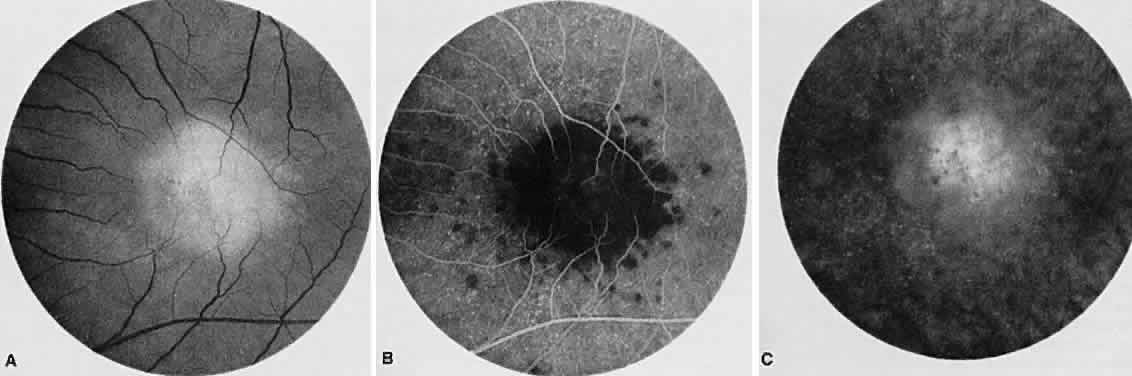

Fig. 2. Vogt-Koyanagi-Harada syndrome. (A) Fundus photograph of the right eye and (B) the left eye showing bullous retinal detachments. (C) Fluorescein angiogram showing multiple hyperfluorescent leaks at the level of the retinal pigment epithelium. (D) Multiple coalescing leaks and fluorescein staining of the subretinal fluid. Large areas of hyperfluorescence involving the entire right posterior pole due to pooling of dye beneath the subretinal space.

Fig. 3. Vogt-Koyanagi-Harada syndrome. A. Fundus photograph of the left eye showing multifocal serous retinal detachment. B. Late fluorescein angiogram showing pooling of dye in the areas of serous detachment. C. Indocyanine angiography showing areas of blocked fluorescence corresponding to serous detachment. More areas of hypofluorescence are noted than those observed on fluorescein angiogram.

There is a characteristic fluorescein angiographic appearance in the early phase showing multiple discrete hyperfluorescent dots at the retinal pigment epithelial level that enlarge over time (see Fig. 2C and D). In the late phase, if there is a serous detachment, the fluorescein pools beneath the subretinal space (see Fig. 3B). The edematous disc hyperfluoresces in the late phase. Generally, the retinal vessels are unaffected.7,8 Retinochoroidal anastomoses also have been documented by fluorescein angiography.9

ICG angiography shows multiple hypofluorescent spots in the posterior pole (see Fig. 3C). These spots may coalesce and obscure the filling of large choroidal vessels. When serous retinal detachment develops, the marked hyperfluorescence observed on FA is not as prominently noted in ICG angiography, presumably because of the highly protein-bound nature of ICG. In fact, diffuse late hypofluorescence may be observed in patients with serous retinal detachment.10 Ill-defined areas of hyperfluorescence corresponding to diffuse choroidal staining may be seen in some cases in the late phases of the angiogram. The optic disc may stain with ICG in the acute phase but usually is minimal compared to that observed on FA.